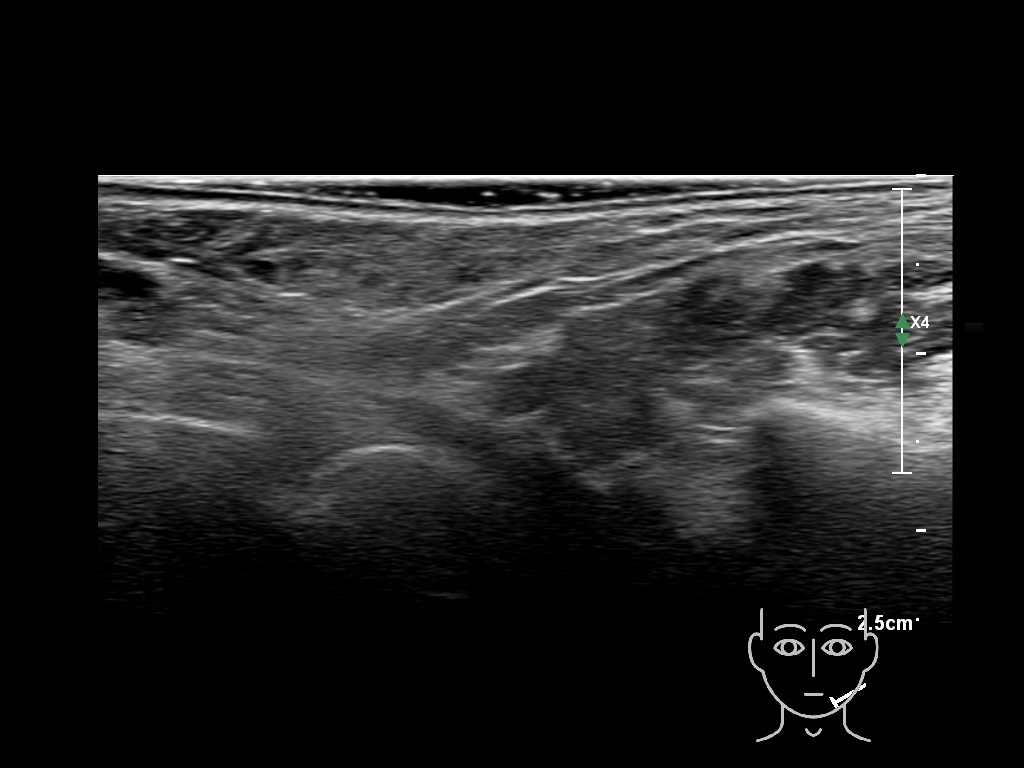

Draw in the image on the right where the fillers are located. To check if your answer is correct, please click on the secondary image.

Fillers

HAca 1b e

HACa 4b e

HACa 5b e